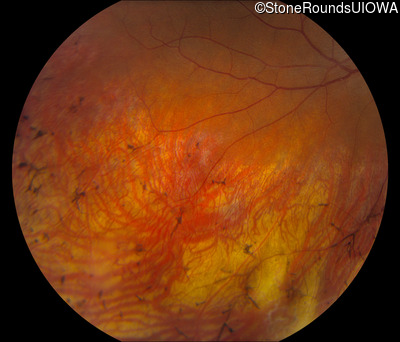

Fundus Photography - Right - 20/30 -2

Exemplar